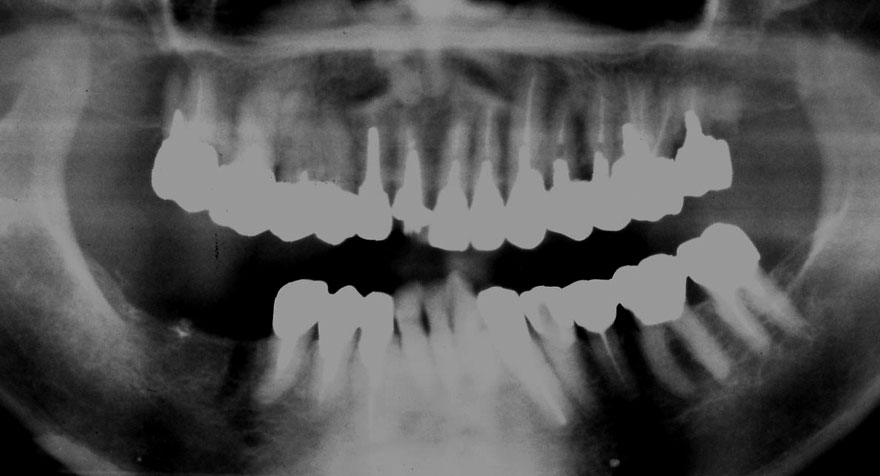

初診時 50歳 女性

30年後 80歳